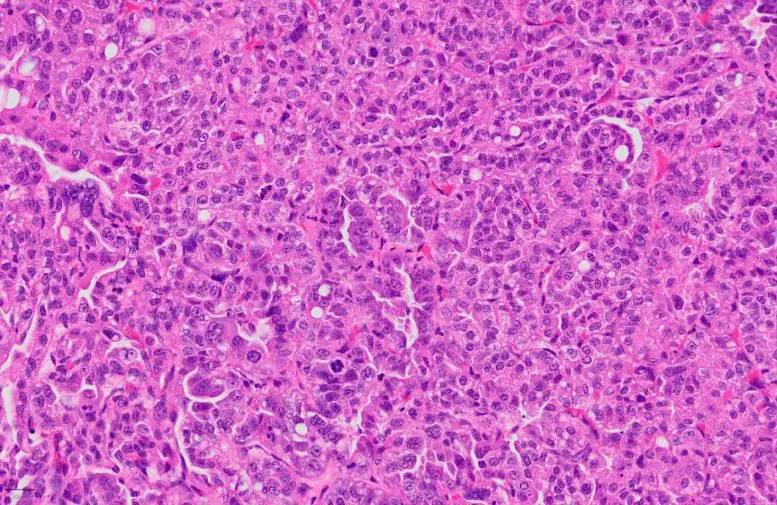

Histological staining of a lung adenocarcinoma, which is made of tumor cells as well as cells of the immune microenvironment including tumor-associated neutrophils. Credit: Caroline Contat (EPFL)

Cancers are not only made of tumor cells. In fact, as they grow, they develop an entire cellular ecosystem within and around them. This “tumor microenvironment” is made up of multiple cell types, including cells of the immune system, like T lymphocytes and neutrophils.

But there is another type of immune cell in the tumor microenvironment whose importance in cancer development has been overlooked: neutrophils, which form part of the body’s immediate or “innate” immune response to microbes. The question, currently debated among scientists, is whether neutrophils help or inhibit the tumor’s growth.